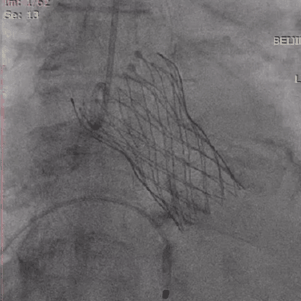

为期两天的手术联播过程中,来自厦门大学心血管病医院王斌教授,首都医科大学附属北京安贞医院宋光远教授,阜外华中心血管病医院王圣教授,南京医科大学第一附属医院孙伟教授,广东省人民医院李捷教授,中国医学科学院阜外医院吴永健教授,中南大学湘雅二医院方臻飞教授,浙江大学医学院附属第二医院王建安教授,北京大学第三医院唐熠达教授分别带来了精彩的TAVR实战案例。

从三叶瓣重度钙化到二叶瓣畸形的根部解剖,从单纯主动脉瓣反流到入路极端迂曲挑战的案例。TaurusOne凭借其优异的柔顺性,支撑力强及内外层双侧裙边的特点,都能从容应对复杂的临床患者解剖结构。从患者的临床选择到术后的长久获益,从手术入路的种类到术中操作的注意事项,从围术期卒中的循证医学到术后的抗凝抗栓用药规范,在线专家共同交流彼此中心的围术期TAVR经验和分享现阶段经导管主动脉瓣置换的诊疗策略。针对当前TAVR领域多个热点学术问题进行了热烈的讨论,现场可谓精彩纷呈、高潮迭起。专家们纷纷借此契机相互交流探讨,分享各自的单中心经验,力求进一步提升TAVR手术的安全性和有效性,为主动脉瓣相关疾病的患者带来长远综合获益。